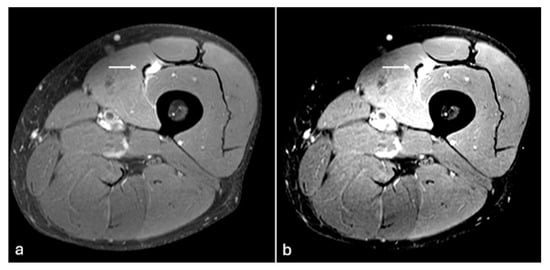

Figure 6. PDFS sagittal images of chest wall (a,b). Soft tissue oedema changes seen in intercostal muscle (arrow) are better delineated with modified windowing (b) in comparison to the default window (a). W/L of image (a)—1704/961, (b)—932/956.